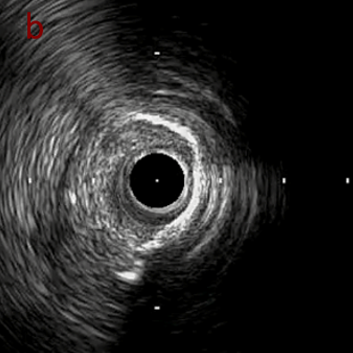

IVUS after OAS low speed 3回

IVUS imaging after low speed 3回

OAS low speedによる引きのsandingを3回行いIVUSを確認するとa-cでは心筋側側へのOASによる良好なbias変化と、それに伴いdの健常側への危険なbias変化を認めた。

そのためcでIVUSマーキングを行い、その点より引きで赤線のpinpoint OAS high speedを行い、dに関してはinjury回避のためにOASを当てない方針とした。